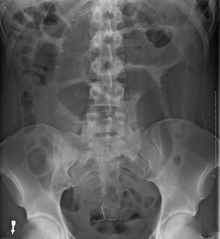

After taking a thorough history, the diagnosis of colonic volvulus is usually easily included in the differential diagnosis. Abdominal plain x-rays are commonly confirmatory for a volvulus, especially if a "bent inner tube" sign or a "coffee bean" sign are seen. These refer to the shape of the air filled closed loop of colon which forms the volvulus. Should the diagnosis be in doubt, a barium enema may be used to demonstrate a "bird's beak" at the point where the segment of proximal bowel and distal bowel rotate to form the volvulus. This area shows an acute and sharp tapering and looks like a bird's beak. If a perforation is suspected, barium should not be used due to its potentially lethal effects when distributed throughout the free infraperitoneal cavity. Gastrografin, which is safer, can be substituted for barium.

- Abdominal x-ray – tire-like shadow arising from right iliac fossa and passing to left